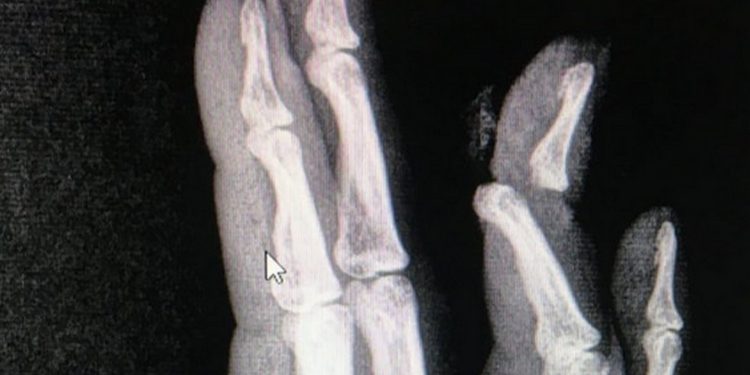

Маалыматка караганда, жабыркаган жигит 20 жашта. Ал кыз менен 2 жыл сүйлөшкөн. Бирок акырында жигит үйлөнүүдөн баш тарткан. Келишпестик чырга айланып, кыз жигиттин манжасын сындырып, сабап салган. Окуя болгон жерге тез жардам кызматы барып, жабырлануучуга керектүү жардам көрсөтүшкөн.